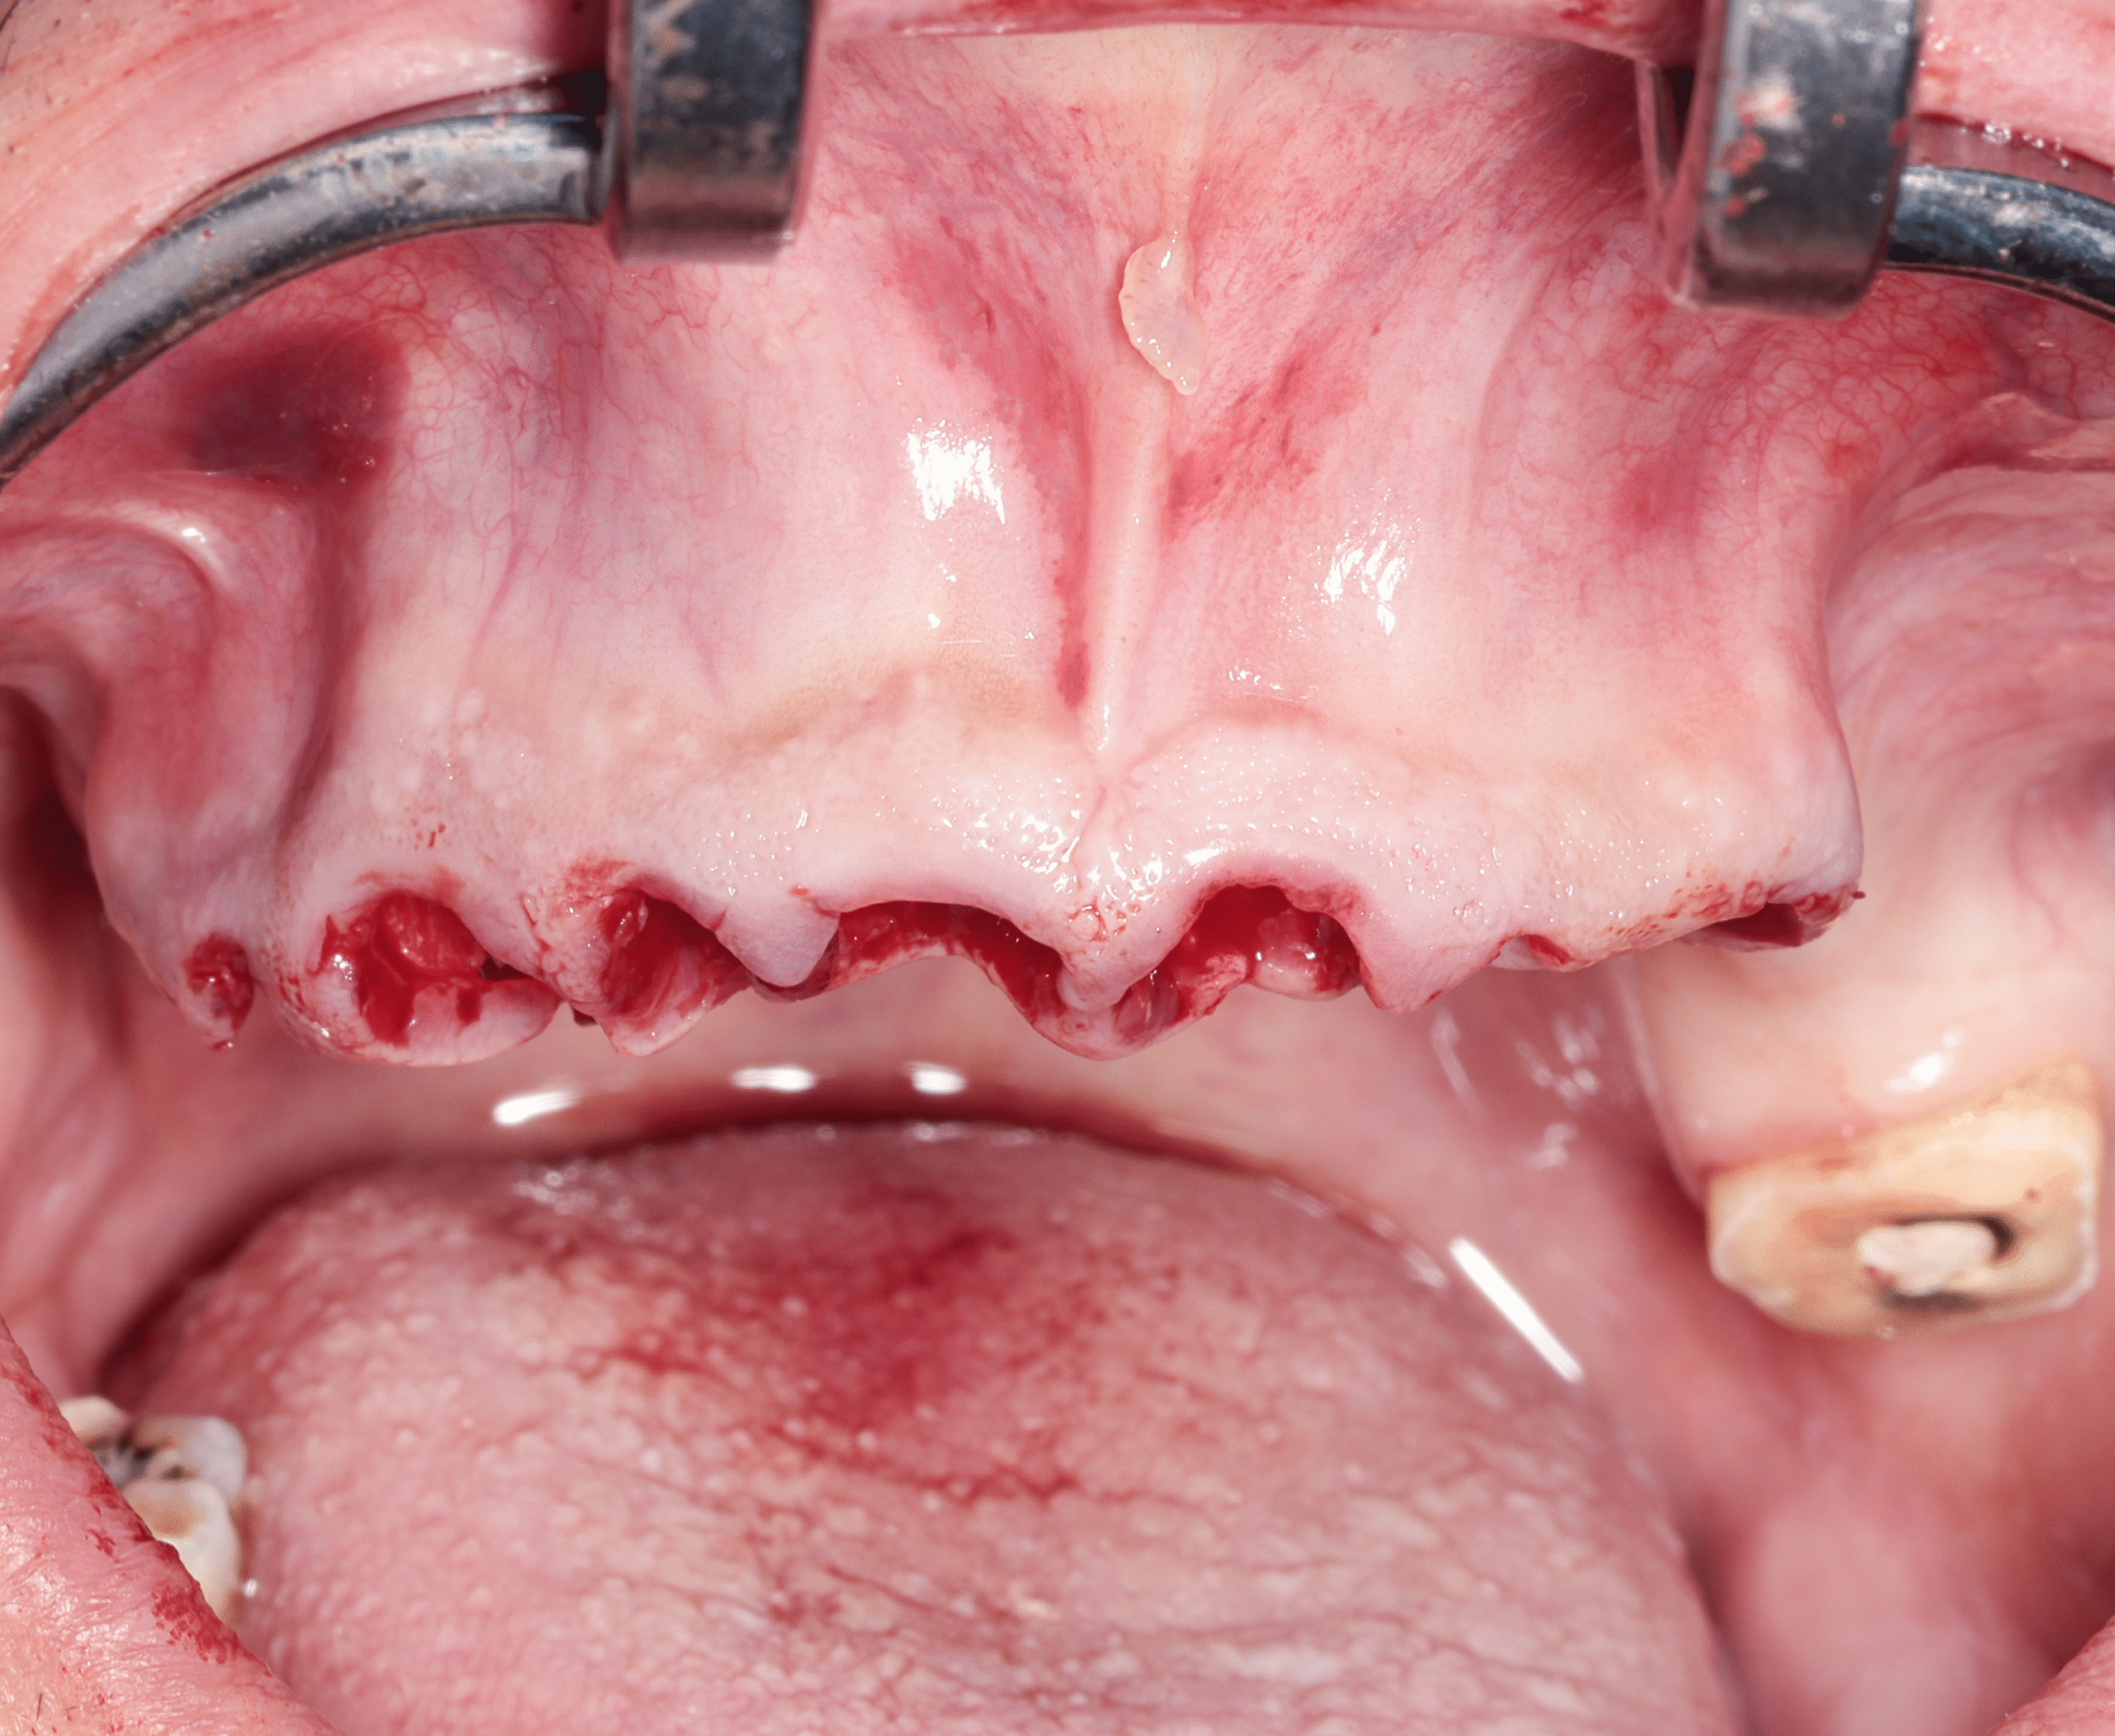

Step 2 — Removal of Remaining Compromised Teeth

- Gentle extraction of non-restorable teeth

- Immediate preparation for implant placement

Step 3 — Strategic Implant Placement (All-on-Four)

- Placement of four implants in each arch

- Angled posterior implants used to maximize available bone without grafting

- Achieved strong primary stability suitable for immediate loading